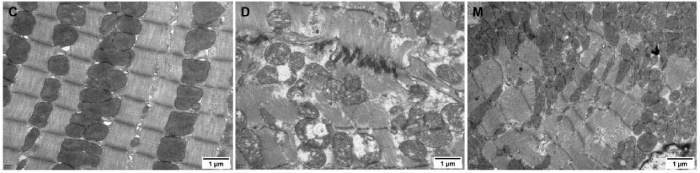

該研究利用透射電鏡測(cè)定了MOTS-c對(duì)糖尿病心肌超微結(jié)構(gòu)的影響。糖尿病引起心肌纖維排列紊亂和線粒體結(jié)構(gòu)的異常改變,包括心肌細(xì)胞排列不規(guī)則、嵴破裂、腫脹和空泡化(圖2)。MOTS-c治療糖尿病大鼠顯著降低心肌線粒體損傷,改善心肌纖維和線粒體結(jié)構(gòu)(圖2)。研究還通過(guò)測(cè)定檸檬酸合酶的活性,測(cè)定了線粒體功能。D組大鼠檸檬酸合酶的活性顯著降低,C組和M組的檸檬酸合酶的活性無(wú)統(tǒng)計(jì)學(xué)差異(圖3g)。

圖2. 各組大鼠心肌組織透射電鏡圖像